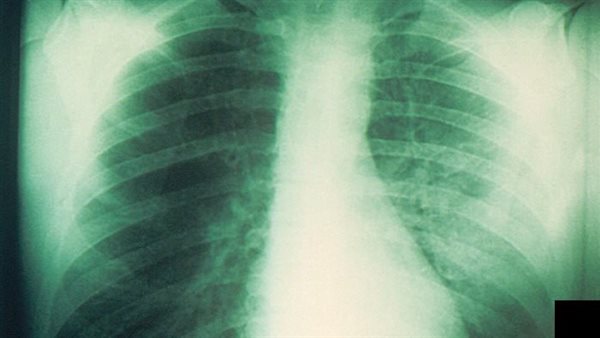

دراسة: العلاج المناعي يعزز البقاء على قيد الحياة بعد جراحة سرطان الرئة

وجدت دراسة جديدة، أن العلاج المناعي، يعزز بقاء مرضى سرطان الرئة في المراحل المبكرة المؤهلين للجراحة عندما يتم دمجه مع العلاج الكيميائي، والدراسة نشرت في مجلة نيو إنجلاند الطبية.

العلاج المناعي يعزز البقاء على قيد الحياة بعد جراحة سرطان الرئة